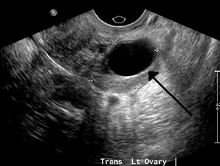

Ovarian cysts are usually diagnosed by either ultrasound, CT scan or MRI, and correlated with clinical presentation and endocrinologic tests as appropriate.

Ultrasound

Follow-up imaging in women of reproductive age for incidentally discovered simple cysts on ultrasound is not needed until 5 cm, as these are usually normal ovarian follicles. For simple cysts greater than 5 cm but less than 7 cm in premenopausal females, cysts should be followed yearly. For simple cysts greater than 7 cm, further imaging with MRI or surgical assessment is mandated as, because of their large size, these cysts cannot be reliably assessed by ultrasound alone. The primary concern for larger cysts is the potential for non-visualization of soft tissue nodularity or thickened septation at their posterior wall due to limited penetrance of the ultrasound beam. For the corpus luteum, a dominant ovulating follicle that typically appears as a cyst with circumferentially thickened walls and crenulated inner margins, follow up is not needed if the cyst is less than 3 cm in diameter. In postmenopausal patients, any simple cyst greater than 1 cm but less than 7 cm needs yearly follow-up, while those greater than 7 cm need MRI or surgical evaluation, similar to reproductive age females.[8]